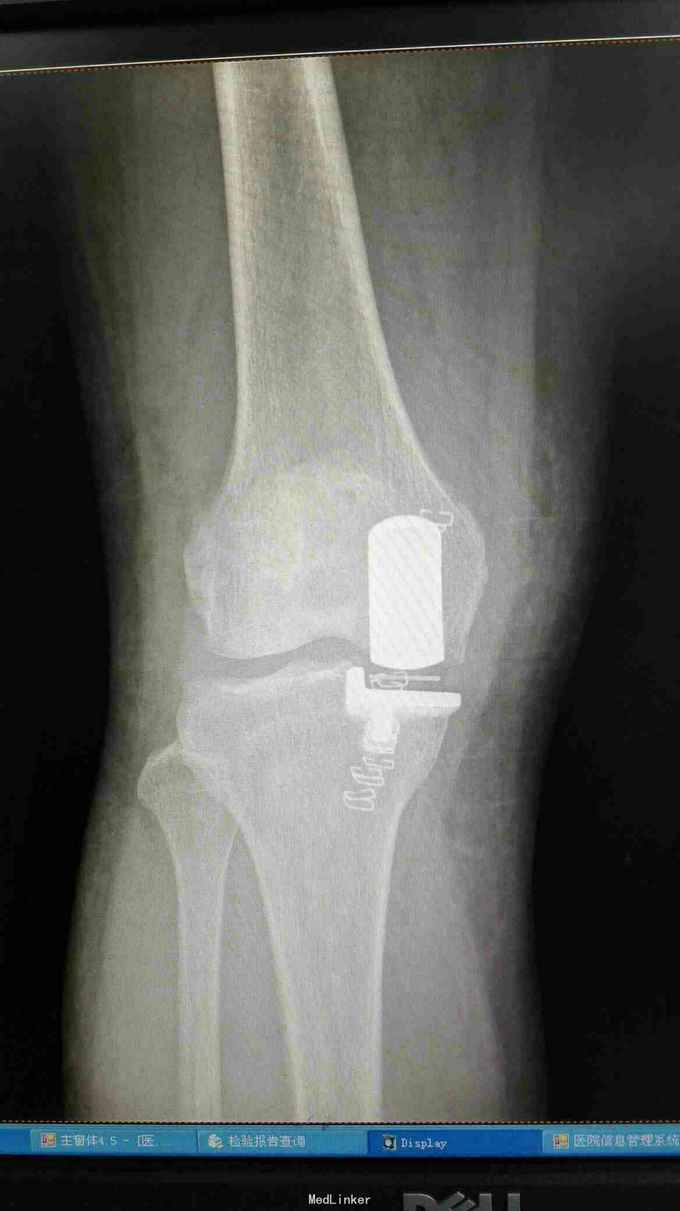

右膝外形正常,皮温正常,右膝内前方压痛(+),前后抽屉试验(-),侧方应力试验(-)、研磨试验内侧(+),关节活动度正常,左膝正常。 站立位膝关节正侧位片提示:右膝关节轻度退行性变,内侧关节间隙稍变窄 右膝关节MRI提示:右股骨内侧髁水肿,考虑局部骨坏死 实验室检查:各炎症指标均正常

诊断:1、右股骨内侧髁骨坏死 2、右膝关节骨性关节炎 治疗:行右膝关节单髁置换术

术后当天下床站立,第二天行走,基本无疼痛,屈伸活动0~120。术后5天出院。 膝关节单髁置换是治疗单侧间室病变有效手段,临床上最常见为膝关节内侧单间室病变,与TKA相比,手术创伤小,恢复快,病人满意度高。行单髁置换满足条件必需是单间室病变,不能太肥胖,韧带完整,可纠正的内外翻畸形及屈曲挛缩小于15度,活动度基本正常。